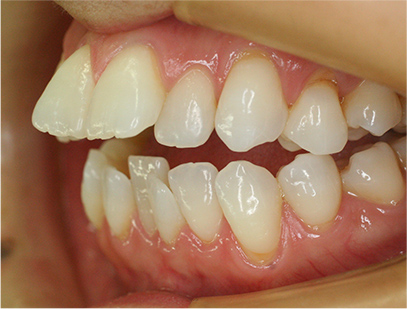

• 右側

• 左側

治療前

• 正面

• 上側

• 下側